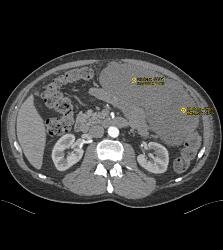

GIST Tumor